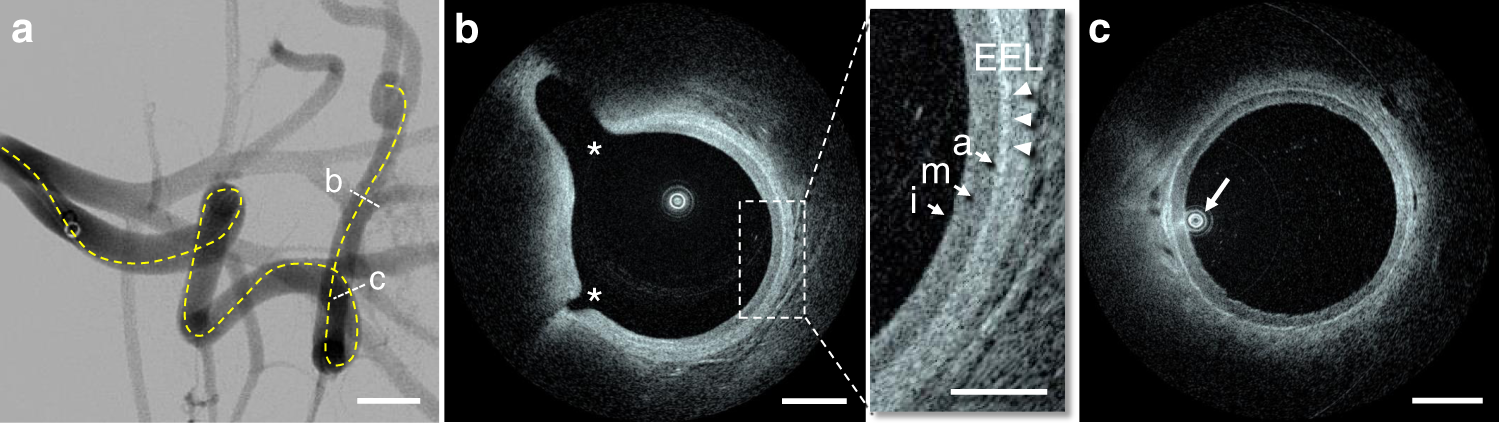

Fig. 2: In vivo imaging in a flexed forelimb model of brachial porcine artery.

a The dotted line highlights the estimated path taken by the Vis-M device through the vessel tortuosity. b HF-OCT microscopy shows the external elastic lamina (arrowheads) and the individual layers of the vessel wall (arrows). A bright tunica intima is followed by a dark tunica media and a bright adventitia (inset). The asterisks denote the ostia of two side-branches, with diameters of ~0.2 and 0.7 mm, respectively. c The arrow indicates the eccentric position of the HF-OCT device in the arterial lumen. The image shows a uniform illumination and absence of NURD artifacts. Imaging in a flexed forelimb swine model was repeated in a total of n = 16 arteries from all animals included in this study (n = 8). The scale bar on DSA image is equal to 1 cm (a). HF-OCT images scale bars are equal to 1 mm (b and c), and 0.5 mm in the inset.